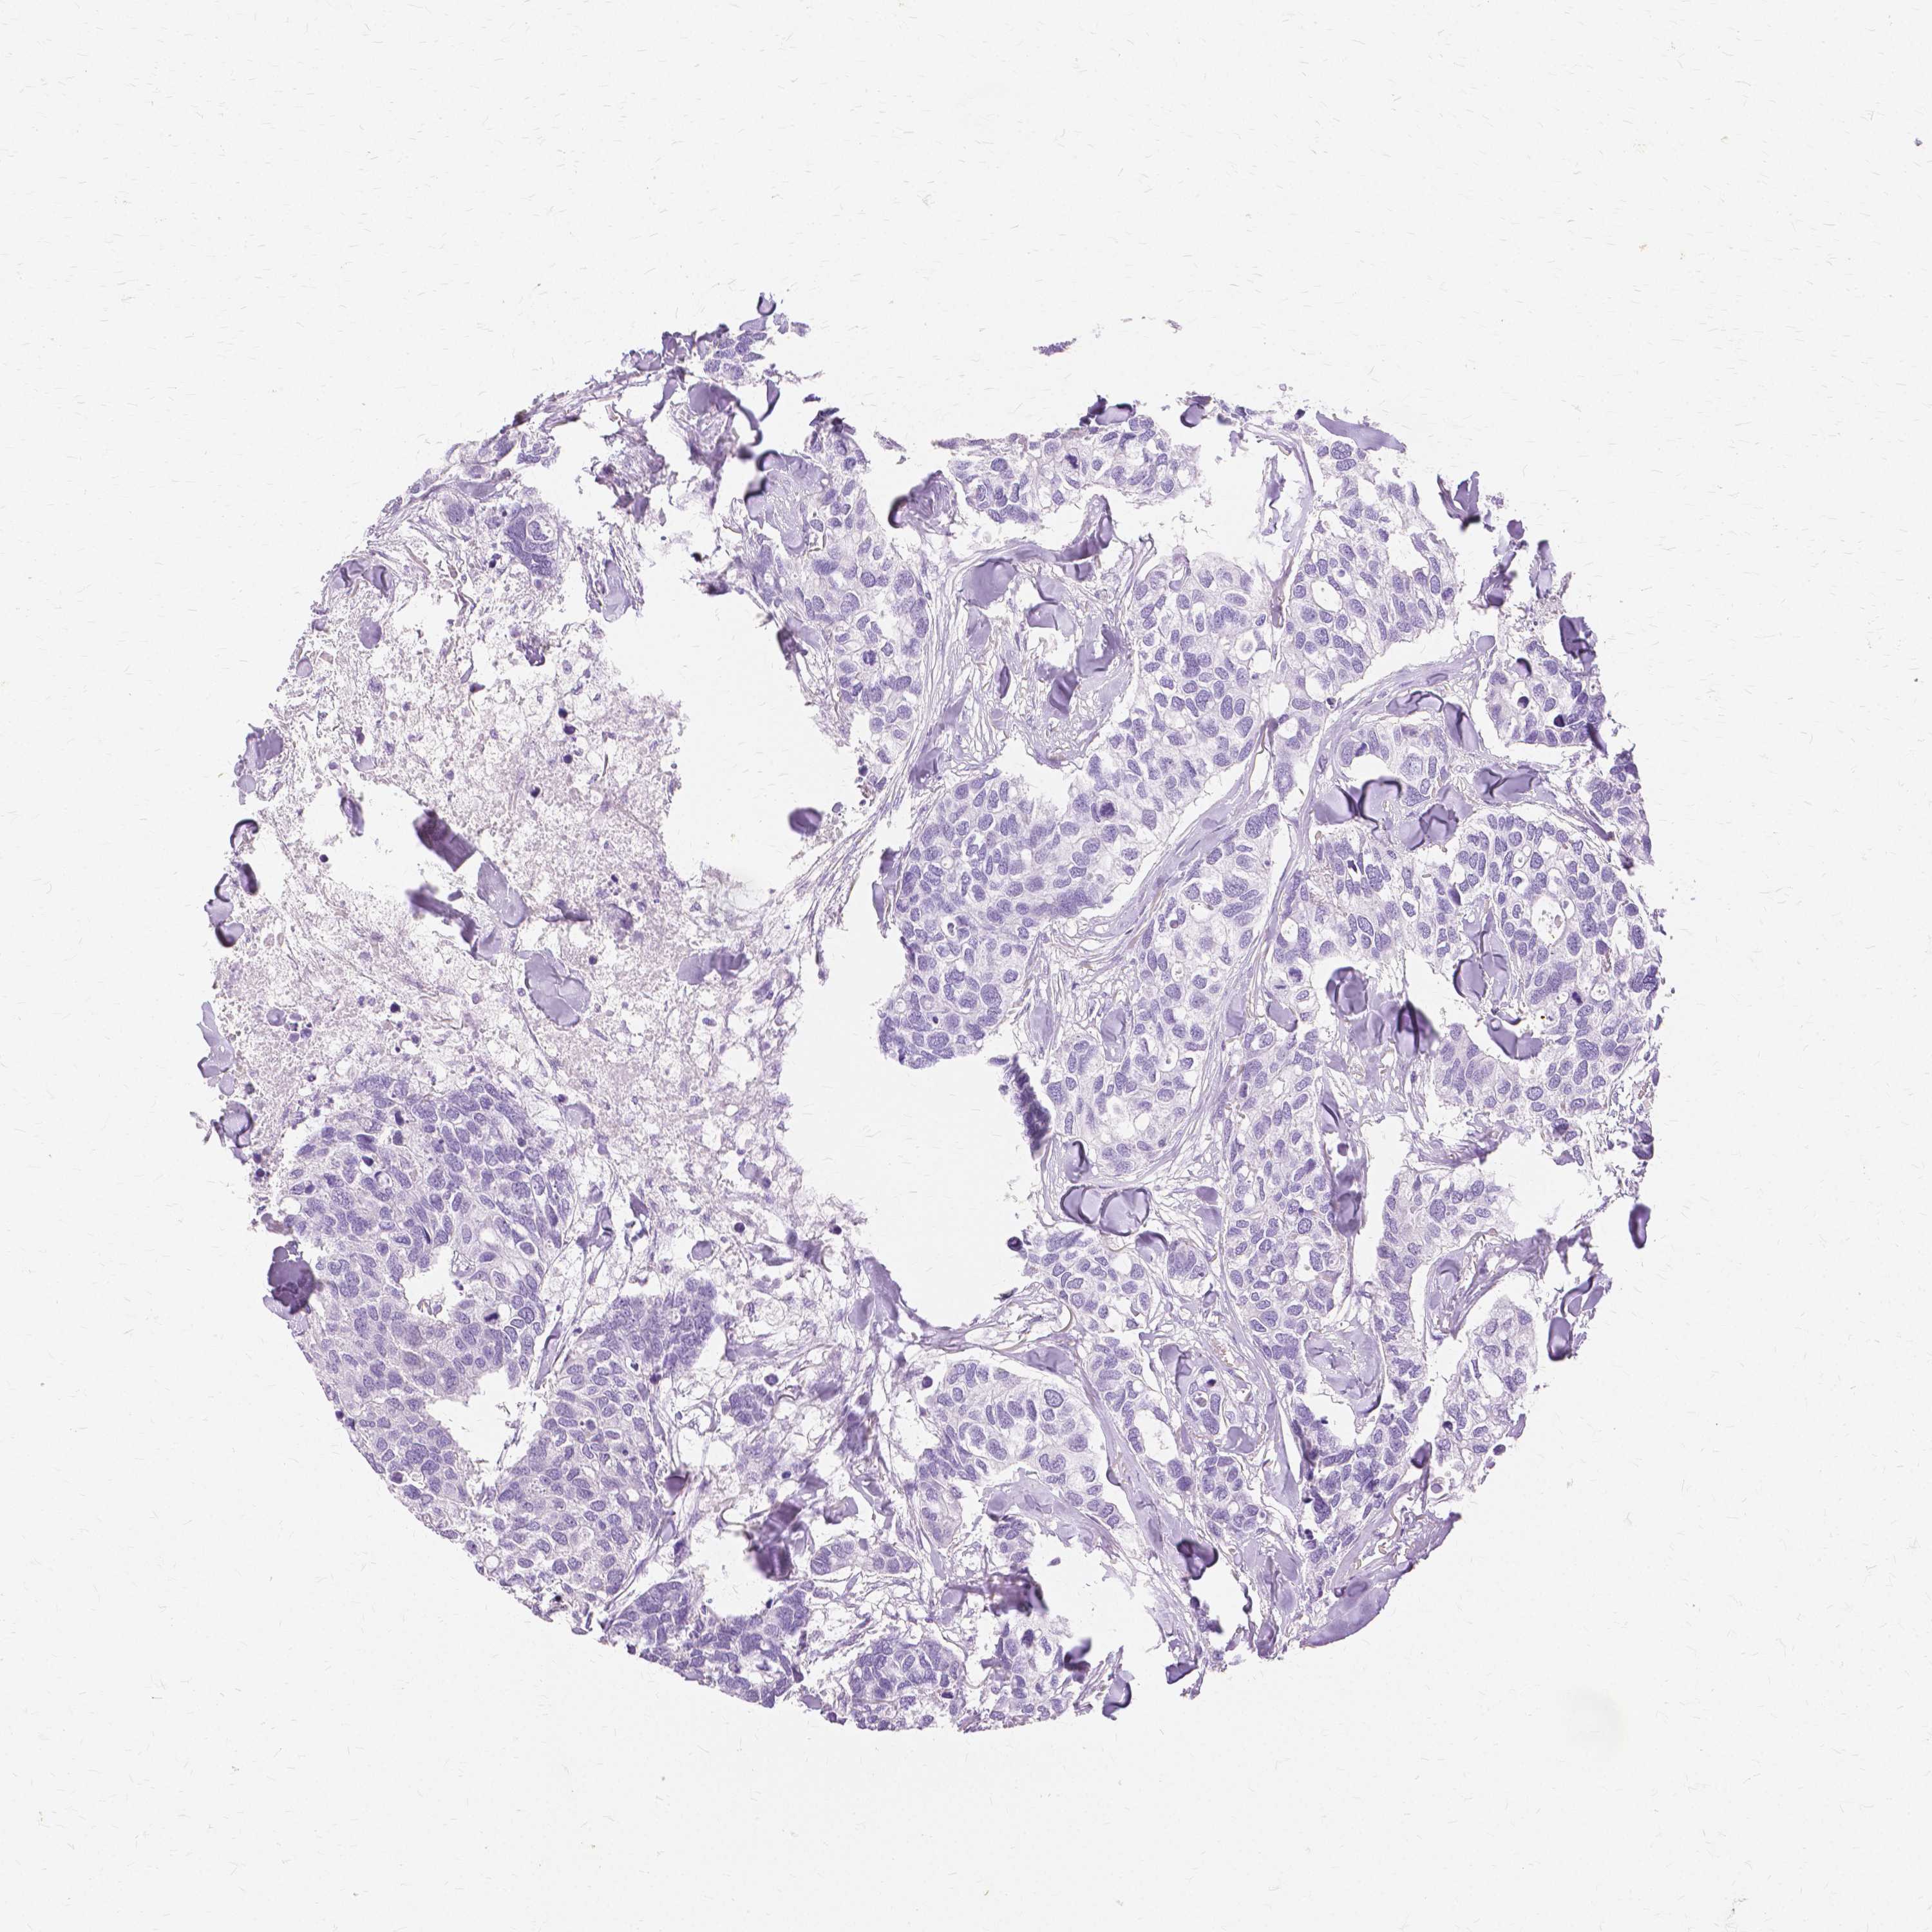

CANCER BREAST CANCER Show tissue menu

BRCA TCGA BRCA VALIDATION PROTEIN EXPRESSION